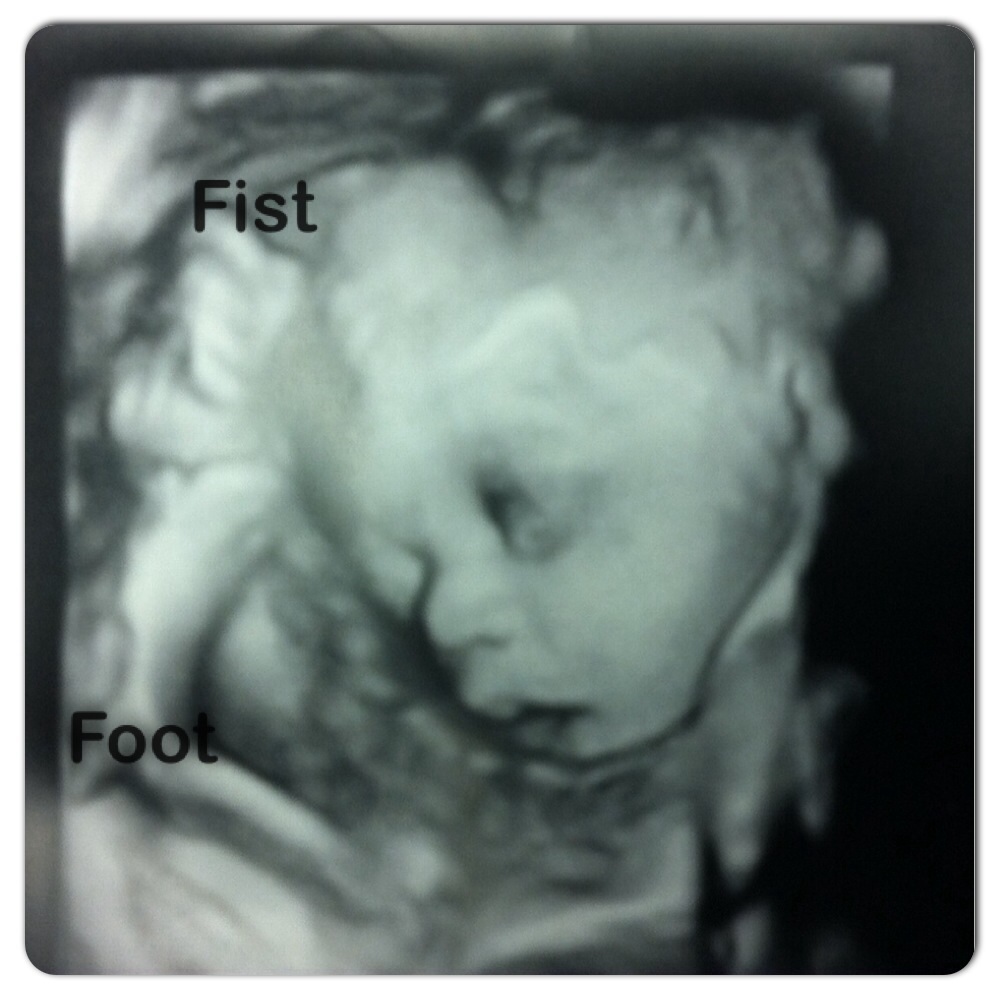

Had an ultrasound done yesterday because women with high blood pressure tend to have smaller babies. Well this is never the case for me being that my first three were ranging from 9lbs to 10lbs. Well I'll be 32 weeks Friday and my baby is already over 5lbs. I have to go back in a month to check her growth.

• Beautiful picture! I've delivered a 10.1 and two sets of twins from 11-12 pounds total weight. I thought I was finished, but out of the blue at the end of spring he said he wanted to try for a baby and here we are. Small babies run in his family so I'm hoping I can spit this one out like a watermelon seed!

• Thanks! :) I'm so ready to have her. She's weighing me down. My frame seems to have gotten smaller and I've lost weight especially during the first trimester. My first born was 10lbs 1oz, my second was 9lbs 3oz and my third was 9lbs, so I expect big babies.